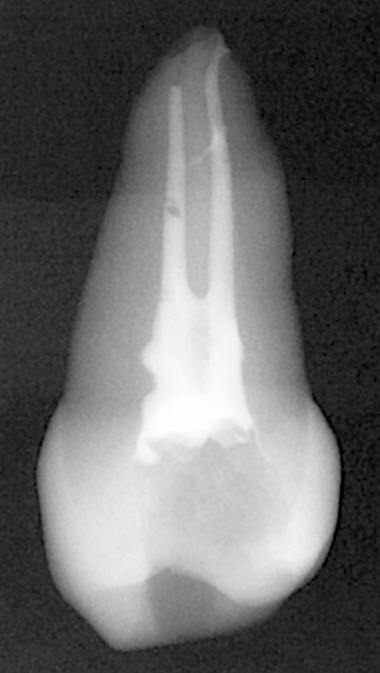

그리고 계속해서, 알파로 끊어낸 부분까지 베타가 다 들어가지 못한 게 또 보인다. 협측 근관이다.

알파 끊어낸 부분까지 베타팁이 다 안들어가는건, 베타팁을 좀 더 얇은 걸 쓰거나 알파 팁을 더 두꺼운 걸 쓰거나 해야하는데

이상하게 지금 알파 팁이 50에 04taper이고, 베타팁이 25G인데 왜 그러는걸까? 25게이지면 50.08아닌가?

아마 알파를 apex-5mm 부근까지 집어넣으면서 GP가 근관 벽에 발라져서, 근관이 좁아지는 게 문제인 것 같기는 하다.

그것도 아니라면, 베타 팁에서 이미 굳은 GP가 나왔기때문에 compaction이 안된걸까? 구개측은 협측에 쏜 이후에 쏴서

잘 연화된 GP가 들어간걸까? 다음번에는 베타 켜고 쏜 첫 GP는 어느정도 제거하고 바로 적용해봐야겠다.

다행히 그래도 알파랑 콘덴서로 잘 compaction 한 덕분에 부근관도 필링이 된 걸 확인할 수 있기는 했다.

협측 근관이 짧아보이는 건 착시 같다 0.5mm까지 잘 들어갔다. 치아자체가 작고, 구개측이 실러때문에 더 길어보여서 그런 것 같다.

구개측 근관은 compaction하면서 실러가 근관공을 넘어갔다. 그렇게 퍼프가 생기면 3차원적으로 다 필링이 된 증거로 본다고 한다.